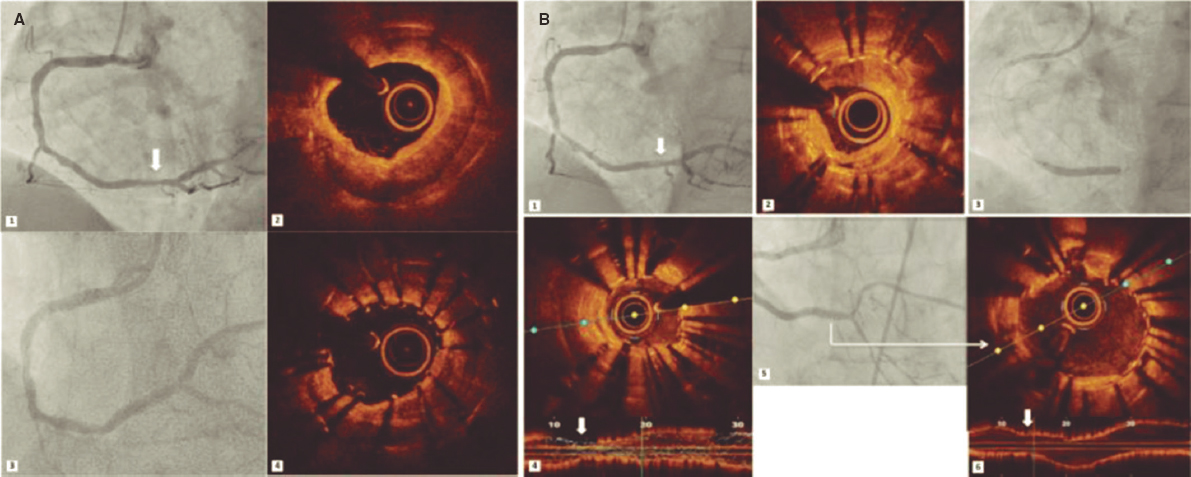

The stent seemed to have been deployed totally outside the right coronary artery, which is why we tried to capture it using a semi- compliant balloon in order to try to drag it towards the radial artery for implantation purposes, but such a maneuver failed (figure 1). This is how we confirmed that the stent was anchored to the ostium by just a few millimeters. Initially the intravascular ultrasound was not used here to assess the location of the stent to avoid any possible moves and manipulations of the implanted stent.

Figure 1. Attempt to drag the stent out of the coronary artery with a semi-compliant balloon.